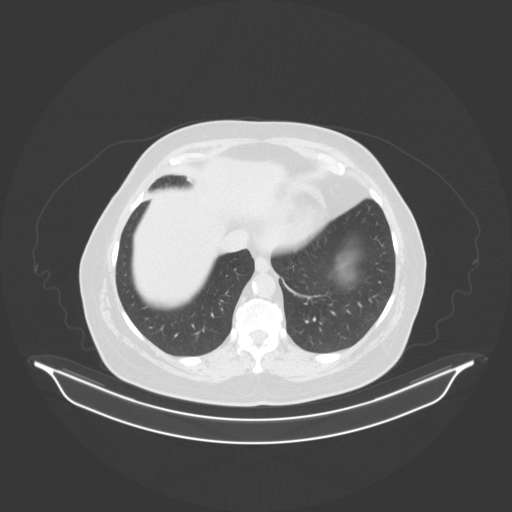

Original NATIVE CT scan (input)

Full window (WL 1023.5, WW 4095 β†’ Low βˆ’1024, High +3071)

Lung window (WL -600, WW 1500 β†’ Low βˆ’1350, High +150)